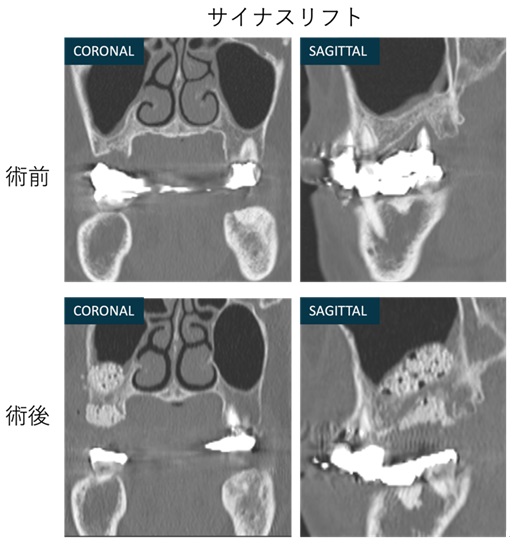

症例② サイナスリフト(上顎洞底挙上術)とGBR(骨誘導再生法)を行なった治療例。